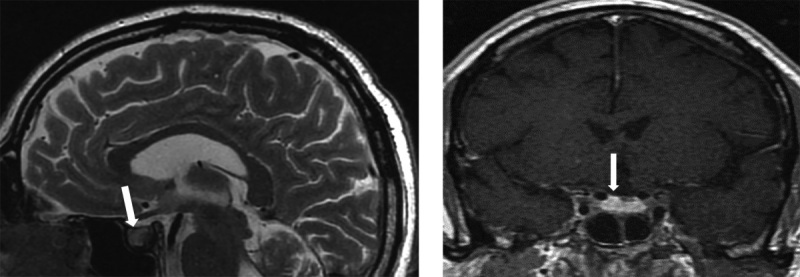

近年来,自身免疫性内分泌疾病的发病率大幅上升,众所周知,这些疾病会影响包括垂体在内的各级内分泌系统。垂体炎是一个通用术语,用于描述任何形式的蝶鞍和蝶鞍上炎症,这些炎症会导致下丘脑-垂体区域的结构发生变化,并表现为垂体前叶和垂体后叶不同程度的激素缺乏。迄今为止,垂体下腺炎有原发性和继发性之分,原发性垂体下腺炎是由于垂体直接遭受自身免疫性病变所致,而继发性垂体下腺炎则是由于存在全身性自身免疫性疾病所致。无论病因如何,垂体功能减退症患者都会表现出由垂体炎症过程引起的各种体征和症状,从而导致垂体功能减退、蝶鞍和蝶鞍旁结构受压。磁共振成像是目前诊断垂体功能减退症的最佳非侵入性诊断工具,但只有通过垂体组织的组织学检查才能确定诊断,而组织学检查需要侵入性方法,这就大大降低了该手术的可行性。在本文中,我们介绍了一名在没有明确临床症状的情况下,核磁共振成像显示有垂体功能减退症迹象的患者。

In recent years, there has been a significant increase in the prevalence of autoimmune endocrinopathies, which are known to affect various levels of the endocrine system, including the pituitary gland. Hypophysitis is a general term used to describe any form of sellar and suprasellar inflammation that leads to structural changes in the hypothalamic-pituitary region and manifests itself in varying degrees of hormonal deficiency of the anterior and posterior pituitary glands. To date, there is a primary form of hypophysitis, which occurs as a result of an autoimmune lesion directly to the pituitary gland, and a secondary form of hypophysitis, which occurs as a result of the presence of a systemic autoimmune disease. Regardless of the etiology, patients with hypophysitis show various signs and symptoms caused by an inflammatory process in the pituitary gland, which can lead to the development of hypopituitarism, compression of the sellar and parasellar structures. MRI is currently the best non-invasive diagnostic tool for diagnosing hypopituitarism, however, the diagnosis can be made with certainty only by histological examination of the pituitary tissue, which requires an invasive approach, which greatly reduces the feasibility of this procedure. In this article, we present a patient with MRI showing signs of hypophysitis in the absence of clear clinical symptoms.